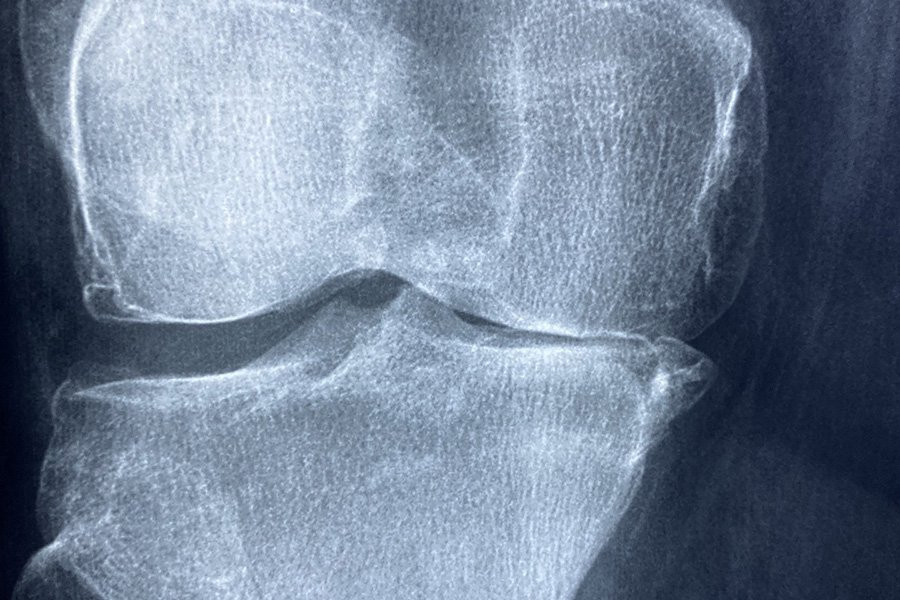

MGP — это специальный белок, содержащийся в кровеносных сосудах и хрящах, который помогает предотвратить затвердевание этих тканей в организме. Если MGP полностью отсутствует, это может привести к синдрому Койтеля — редкому состоянию, при котором ткани кальцифицируются, вызывая проблемы со скелетом и кровеносными сосудами.

После тестирования этих генетических изменений на мышах, чтобы лучше понять ситуацию на клеточном и молекулярном уровнях, исследователи обнаружили, что измененный MGP вызывает аналогичные проблемы с костями как у мышей, так и у людей. В отличие от нормального белка, измененный белок не выходит из клеток, что, в свою очередь, приводит к стрессу в части клетки, называемой эндоплазматической сетью. Хрящевые клетки, вырабатывающие измененный белок, не могут справиться со стрессом и в конечном итоге погибают, вызывая аномалии костей.